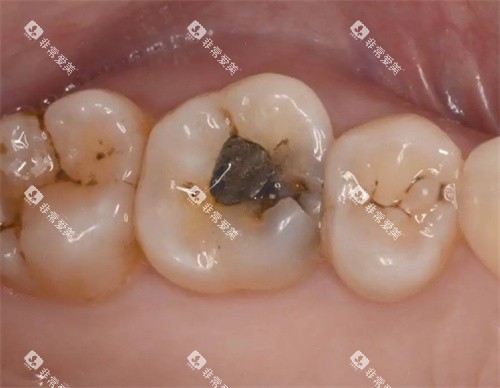

例如,在补牙时,医生会告知患者不同补牙材料的优缺点,让患者根据自己的情况做出选择。

而传统金属牙套在进食时容易残留食物残渣,清洁起来比较困难,长期下去可能会导致龋齿、牙周炎等口腔问题。